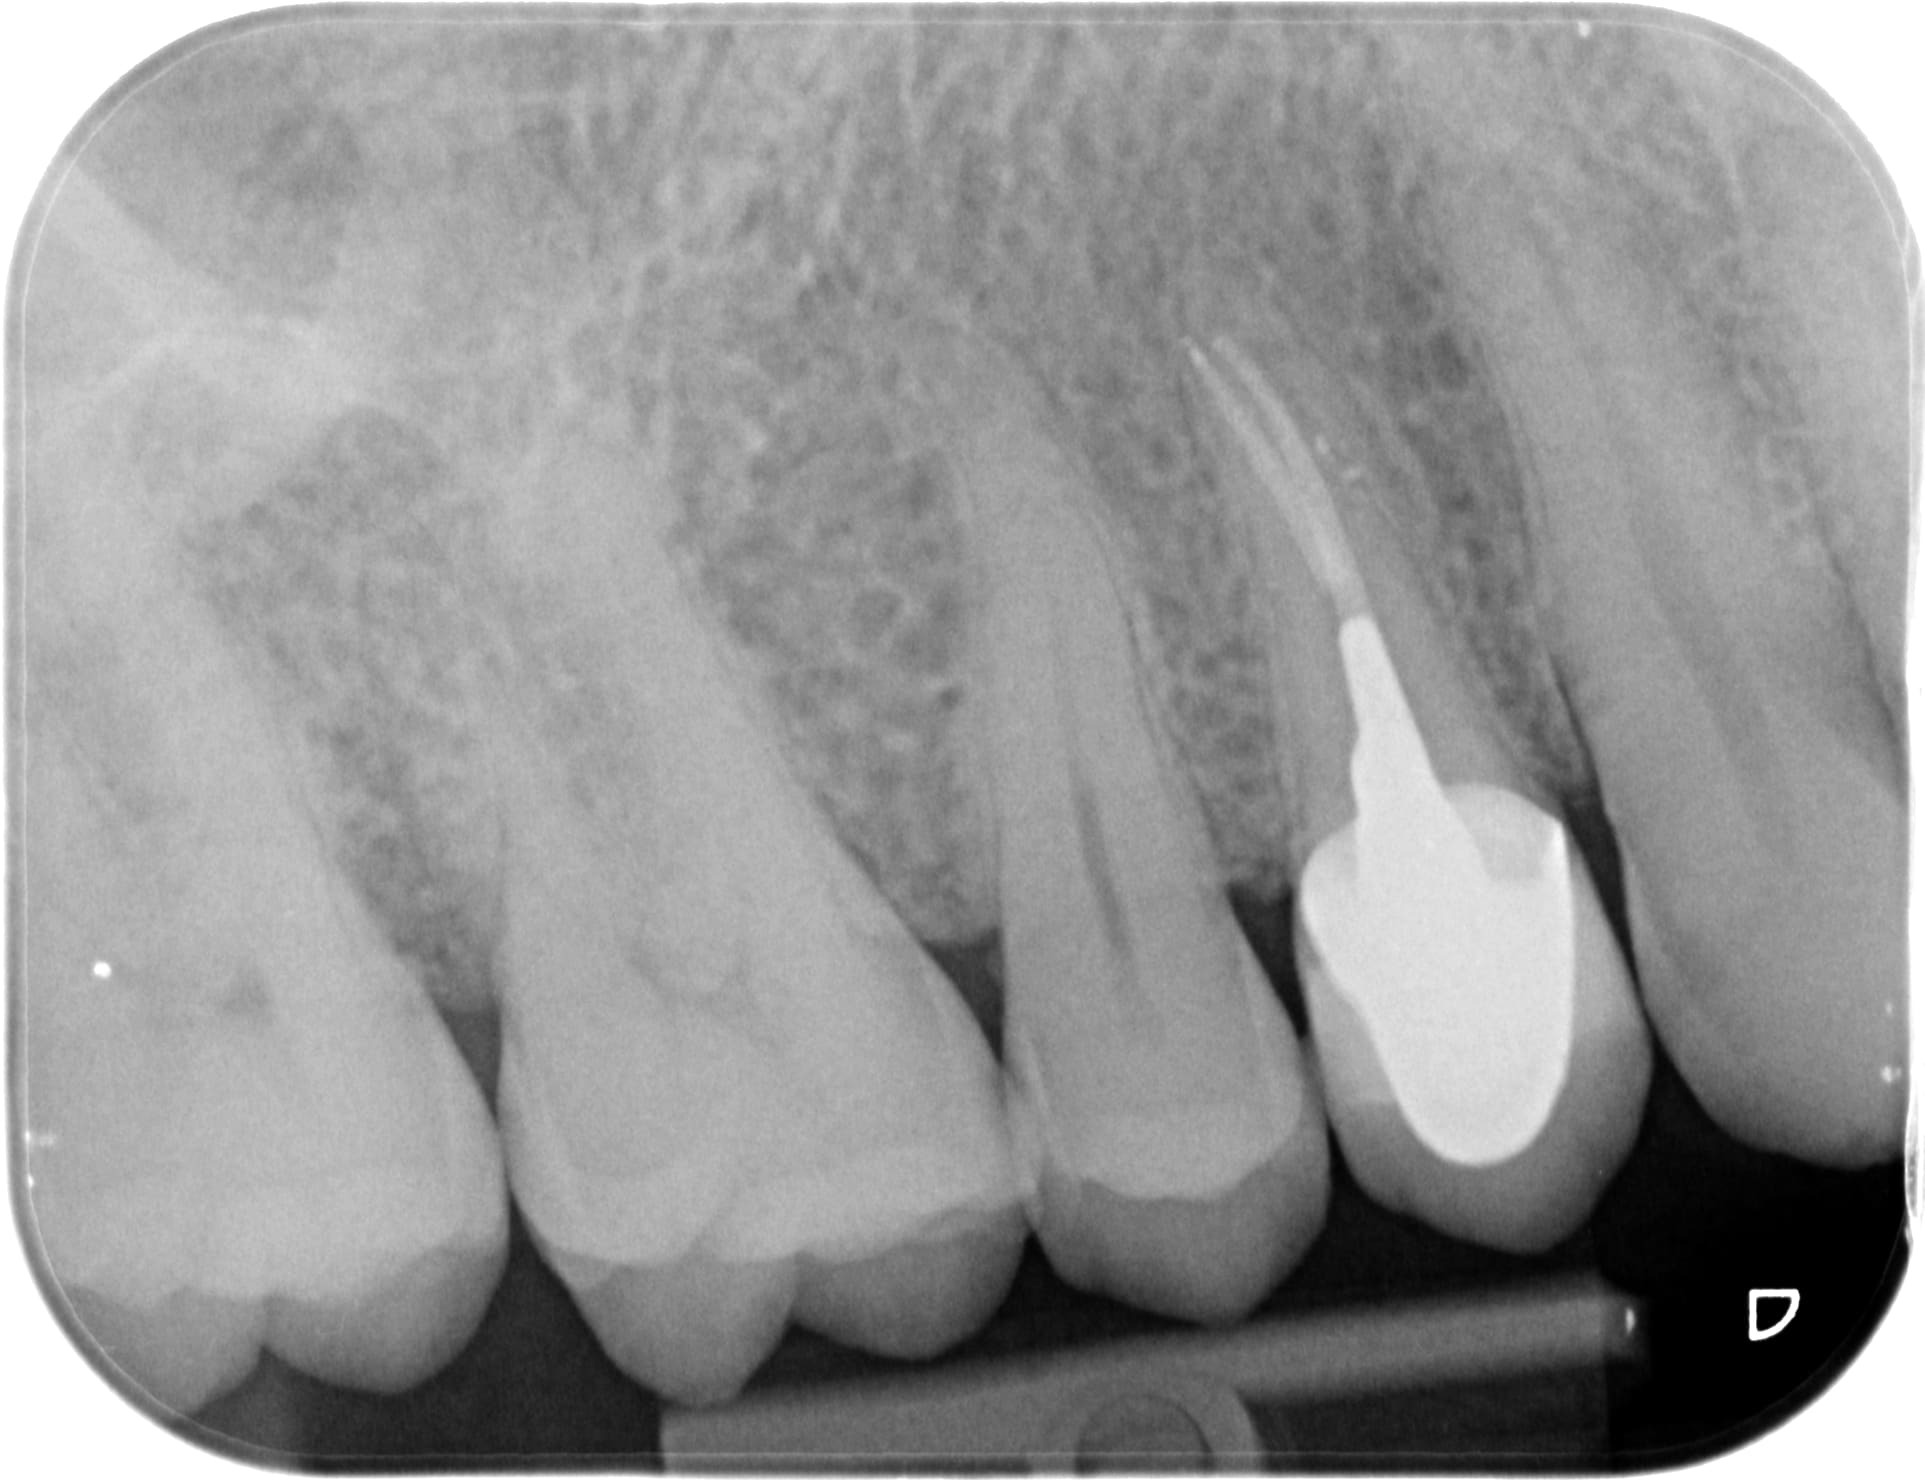

1er rdv 40min endo taille empreinte clip voco (je sais pas si je pourrais le coter 25e en janvier mais pourquoi pas?)

2nd rdv 20min pose de la chinoiserie (ic+ccm 90e...)

Honoraires: 48.20 endos + 15.96 radio + 2x28.92 det (lol) + 129.80 IC + 410e de ccm

662e d'honoraires, 90e de frais de prothèse, 1h de travail. Bienvenue dans le RA.

1513 x 20171006 172319 x9hxynwtya8k 4 wofe6p - Eugenol

1513 x 20170908 152454 x3droyelajju 4 da6flu - Eugenol

20171006 202552 p5wrww - Eugenol

20171006 202647 c5rk4d - Eugenol

Tres tres propre du debut à la fin , cette chinoiserie Hoku .